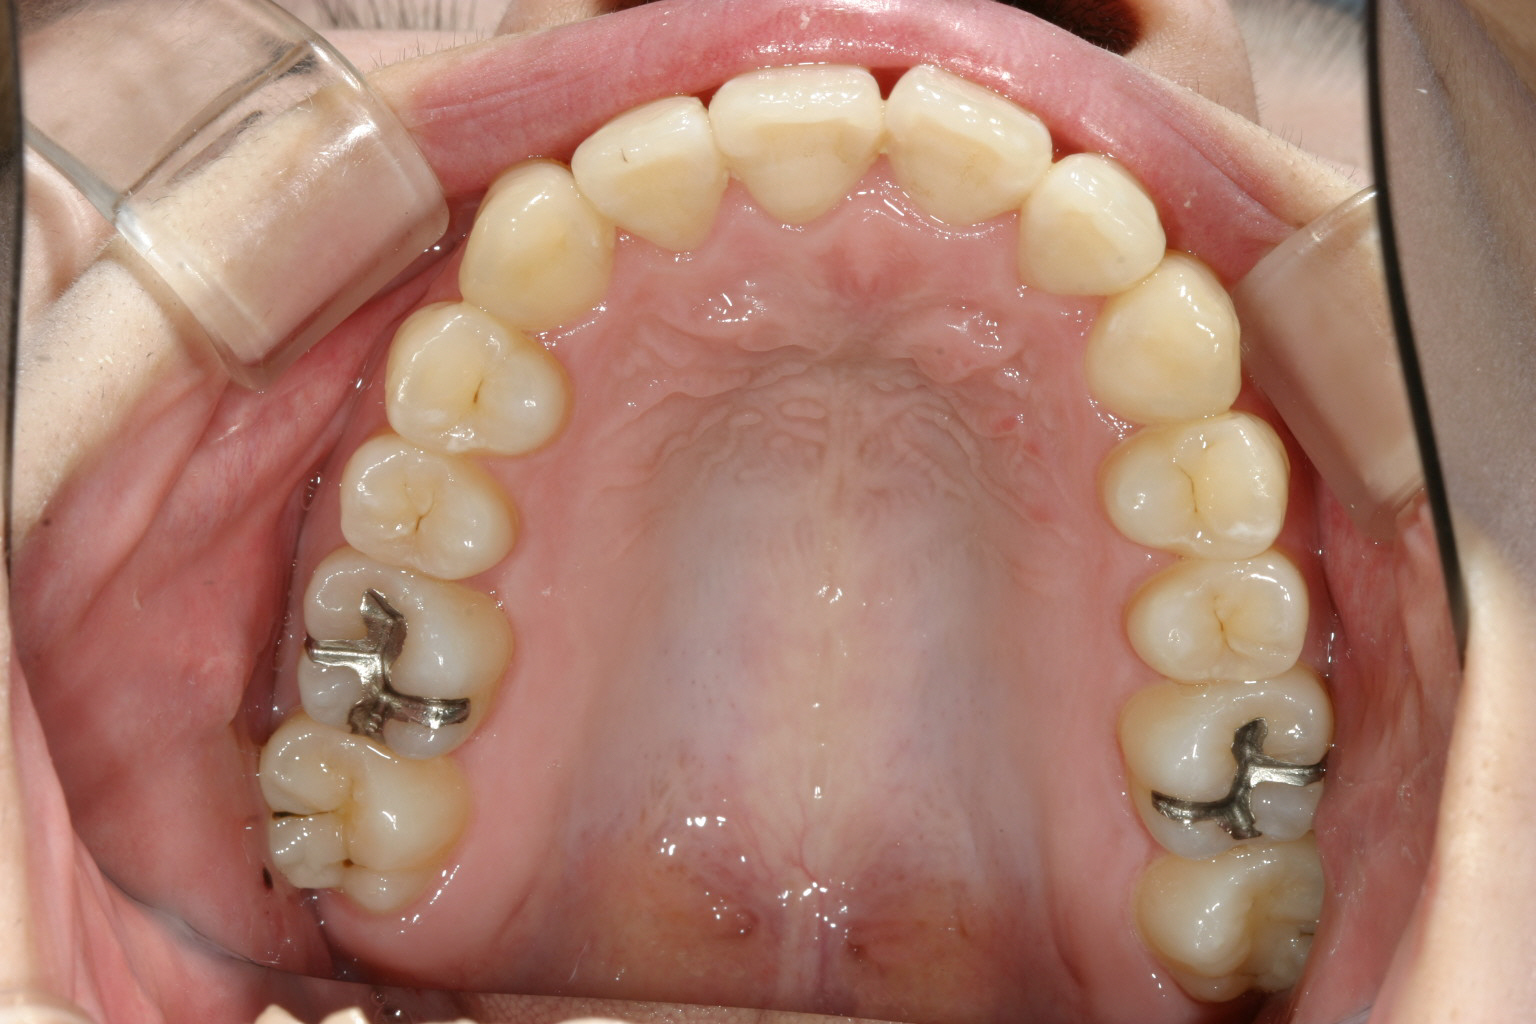

アーチをU字に広げ多少のIPR(隙間削合)を行っています。

綺麗なオーバージェットに改善しました。

今回のケースは上下額ともアーチがV字の為U字に出来たガチャガチャを改善しIPRを行い矯正しました。